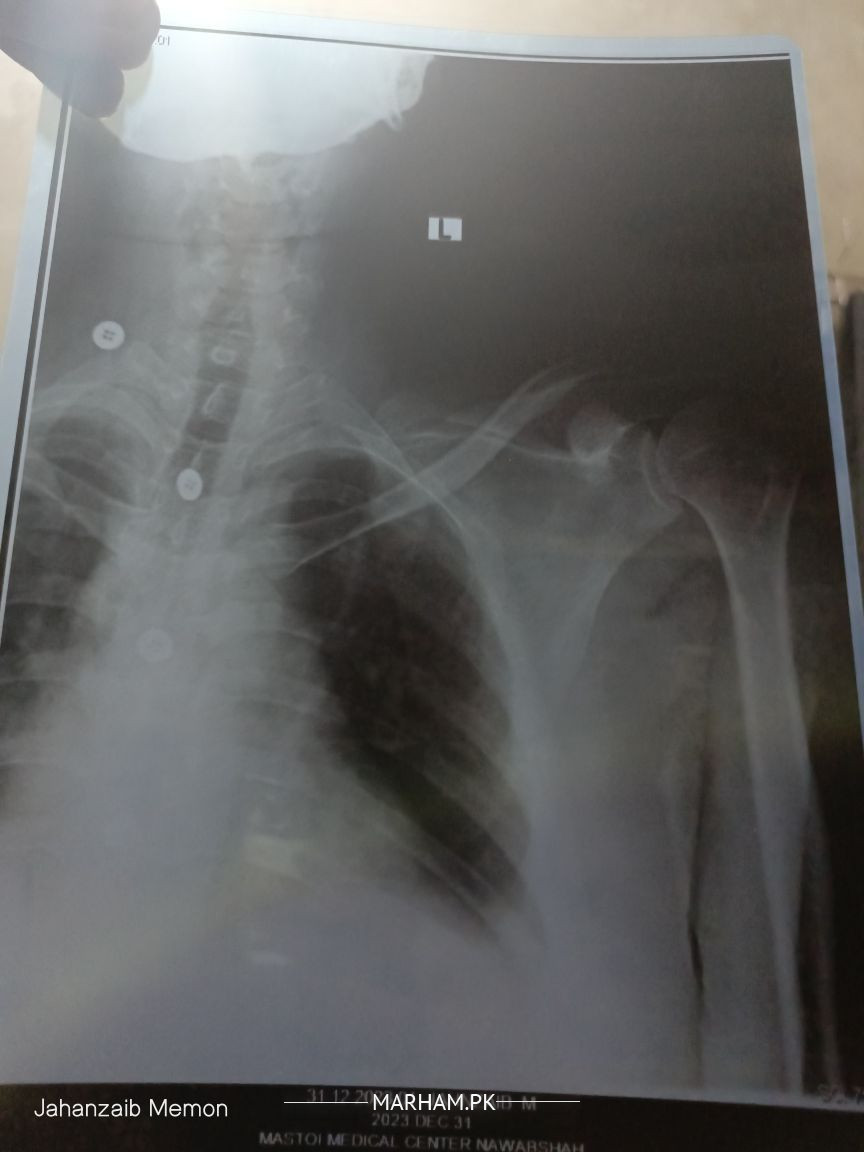

Report bus ye Xray kerwaya he jo attach kia he

g report mae cervical issue hae ..Jo treatable hae